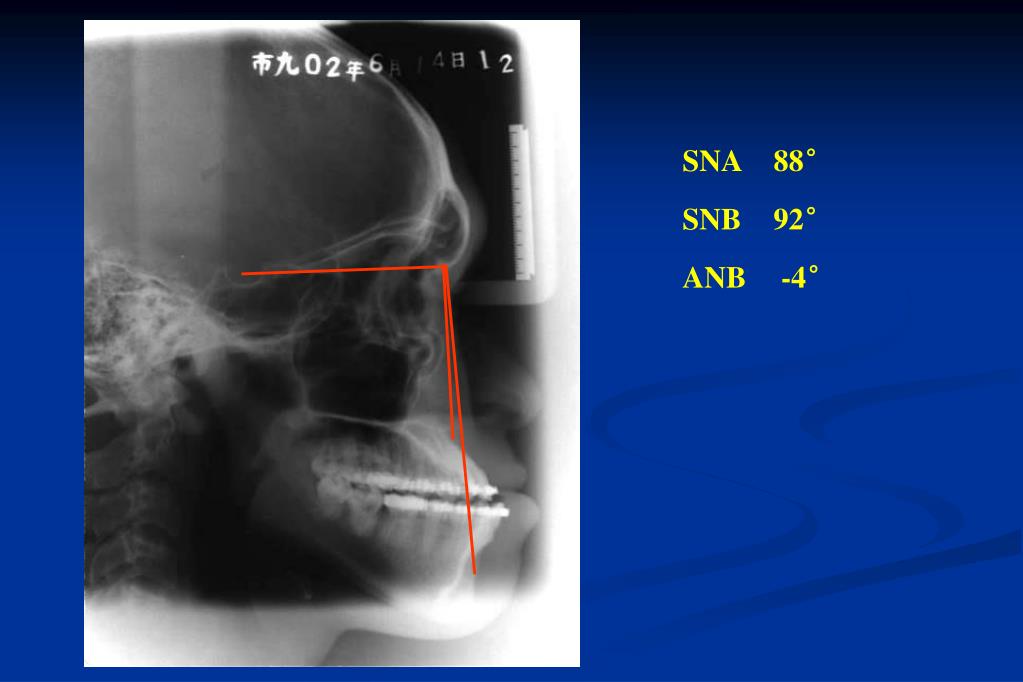

26. Pre operation & after presurgical orthodontic treatment

27. SNA 88° SNB 92° ANB -4°